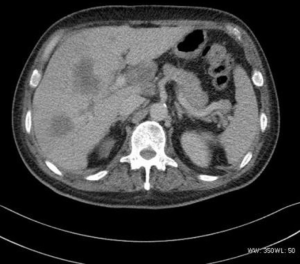

The density was uneven in the five mediastinum tumor cases, which included one case with patchy vcalcification. Four cases had uneven enhancement after the dynamic enhanced scan, and one case exhibited obvious enhancement. All five cases had lymph node metastasis. Furthermore, one case had multiple metastases of the bilateral lungs, subpleural, liver, and bone (Figure 3), and one case had involvement of the left and right pulmonary arteries and superior vena cava. In two cases the metastasis involved the pericardium and mediastinum pleura.